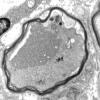

20E1 Suprascapular nerve (Case 20) EM 013A - Copy

20E2 Suprascapular nerve (Case 20) EM 021A - Copy

20E3 Suprascapular nerve (Case 20) EM 024A - Copy

20E4 Suprascapular nerve (Case 20) EM 025A - Copy